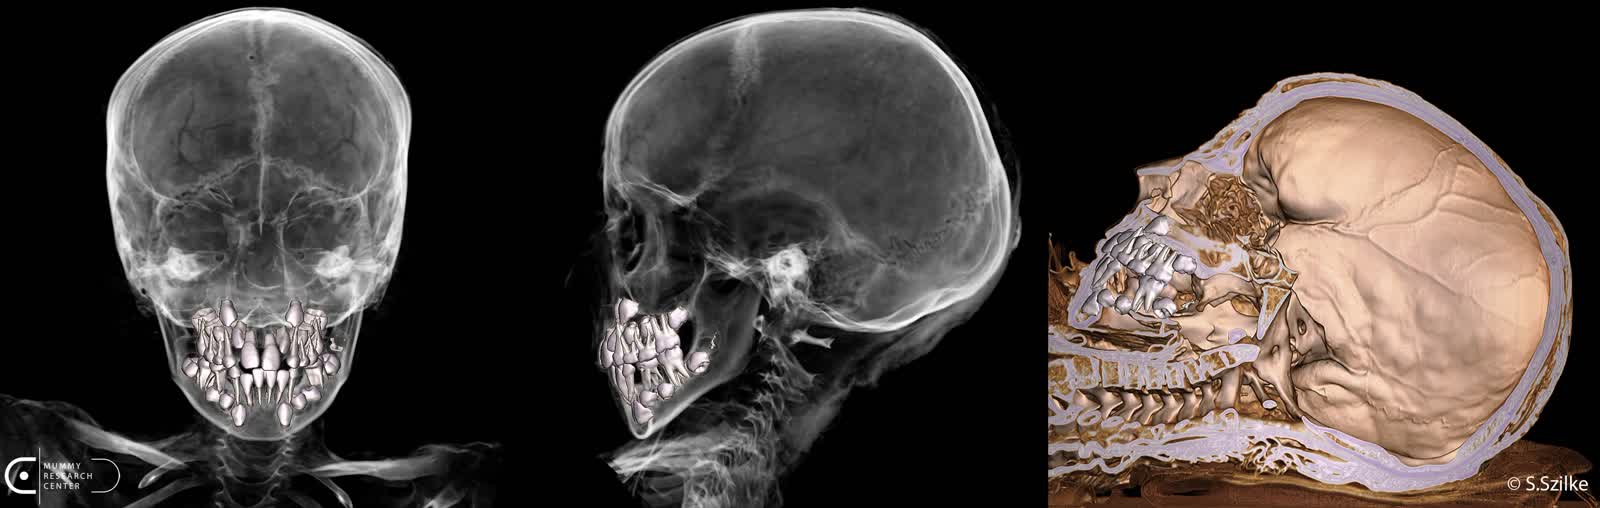

Naukowcy dzięki zaawansowanej technologii zajrzeli niejako do wnętrza mumii, o czym mówi kierownik Zakładu Diagnostyki Obrazowej i Radiologii Zabiegowej Maciej Mazgaj.

– Mieliśmy pełną świadomość, że od 2000 lat nikt tego wnętrza nie oglądał. Doskonale zachowany kościec, co było dla mnie też sporym zaskoczeniem. Wszyscy znamy obraz mumii z zewnątrz, jak one wyglądają. Natomiast to, że kryją w środku tak doskonale zachowane struktury kostne było dla mnie dużym pozytywnym zaskoczeniem. Tutaj akurat, w tym konkretnym przypadku, również tkanki miękkie były zachowane w taki sposób, mówię o skórze, że można było bez problemu rozpoznać płeć chłopca.

– Dzięki dotychczas przeprowadzonym badaniom jesteśmy w stanie dokładnie zrekonstruować ciało zmumifikowanego chłopca – mówi prezes Fundacji Mummy Research Center Marzena Ożarek-Szilke. – Jesteśmy w stanie wydrukować szkielet, jesteśmy w stanie wydrukować każdy element mumii w tej chwili. Już zrobiliśmy wirtualną autopsję, można ją zobaczyć na YouTube Fundacji Mummy Research Center. Poza tym jeszcze takie badania pozwalają na stworzenie, powiedzmy, takiego korpusu, wydrukowanie mumii, na którą będzie można zdjąć kartonaż. Bo teraz największym wyzwaniem, jakie stoi przed nami, to jest konserwacja tej mumii, dlatego że kartonaż jest w bardzo złym stanie. On został w pewnym etapie przechowywania muzealnego posklejany taśmą, taką zwykłą taśmą malarską, która jest naklejana bezpośrednio na malowidła.